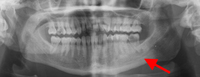

Panoramic radiograph showing decayed bilateral mandibular third molars and failed root canal treatment with periapical lesion related to the right mandibular first molar (middle arrow); also shows carious bilateral mandibular third molars on both sides

From the personal collection of Melanie S. Lang and Thomas B. Dodson